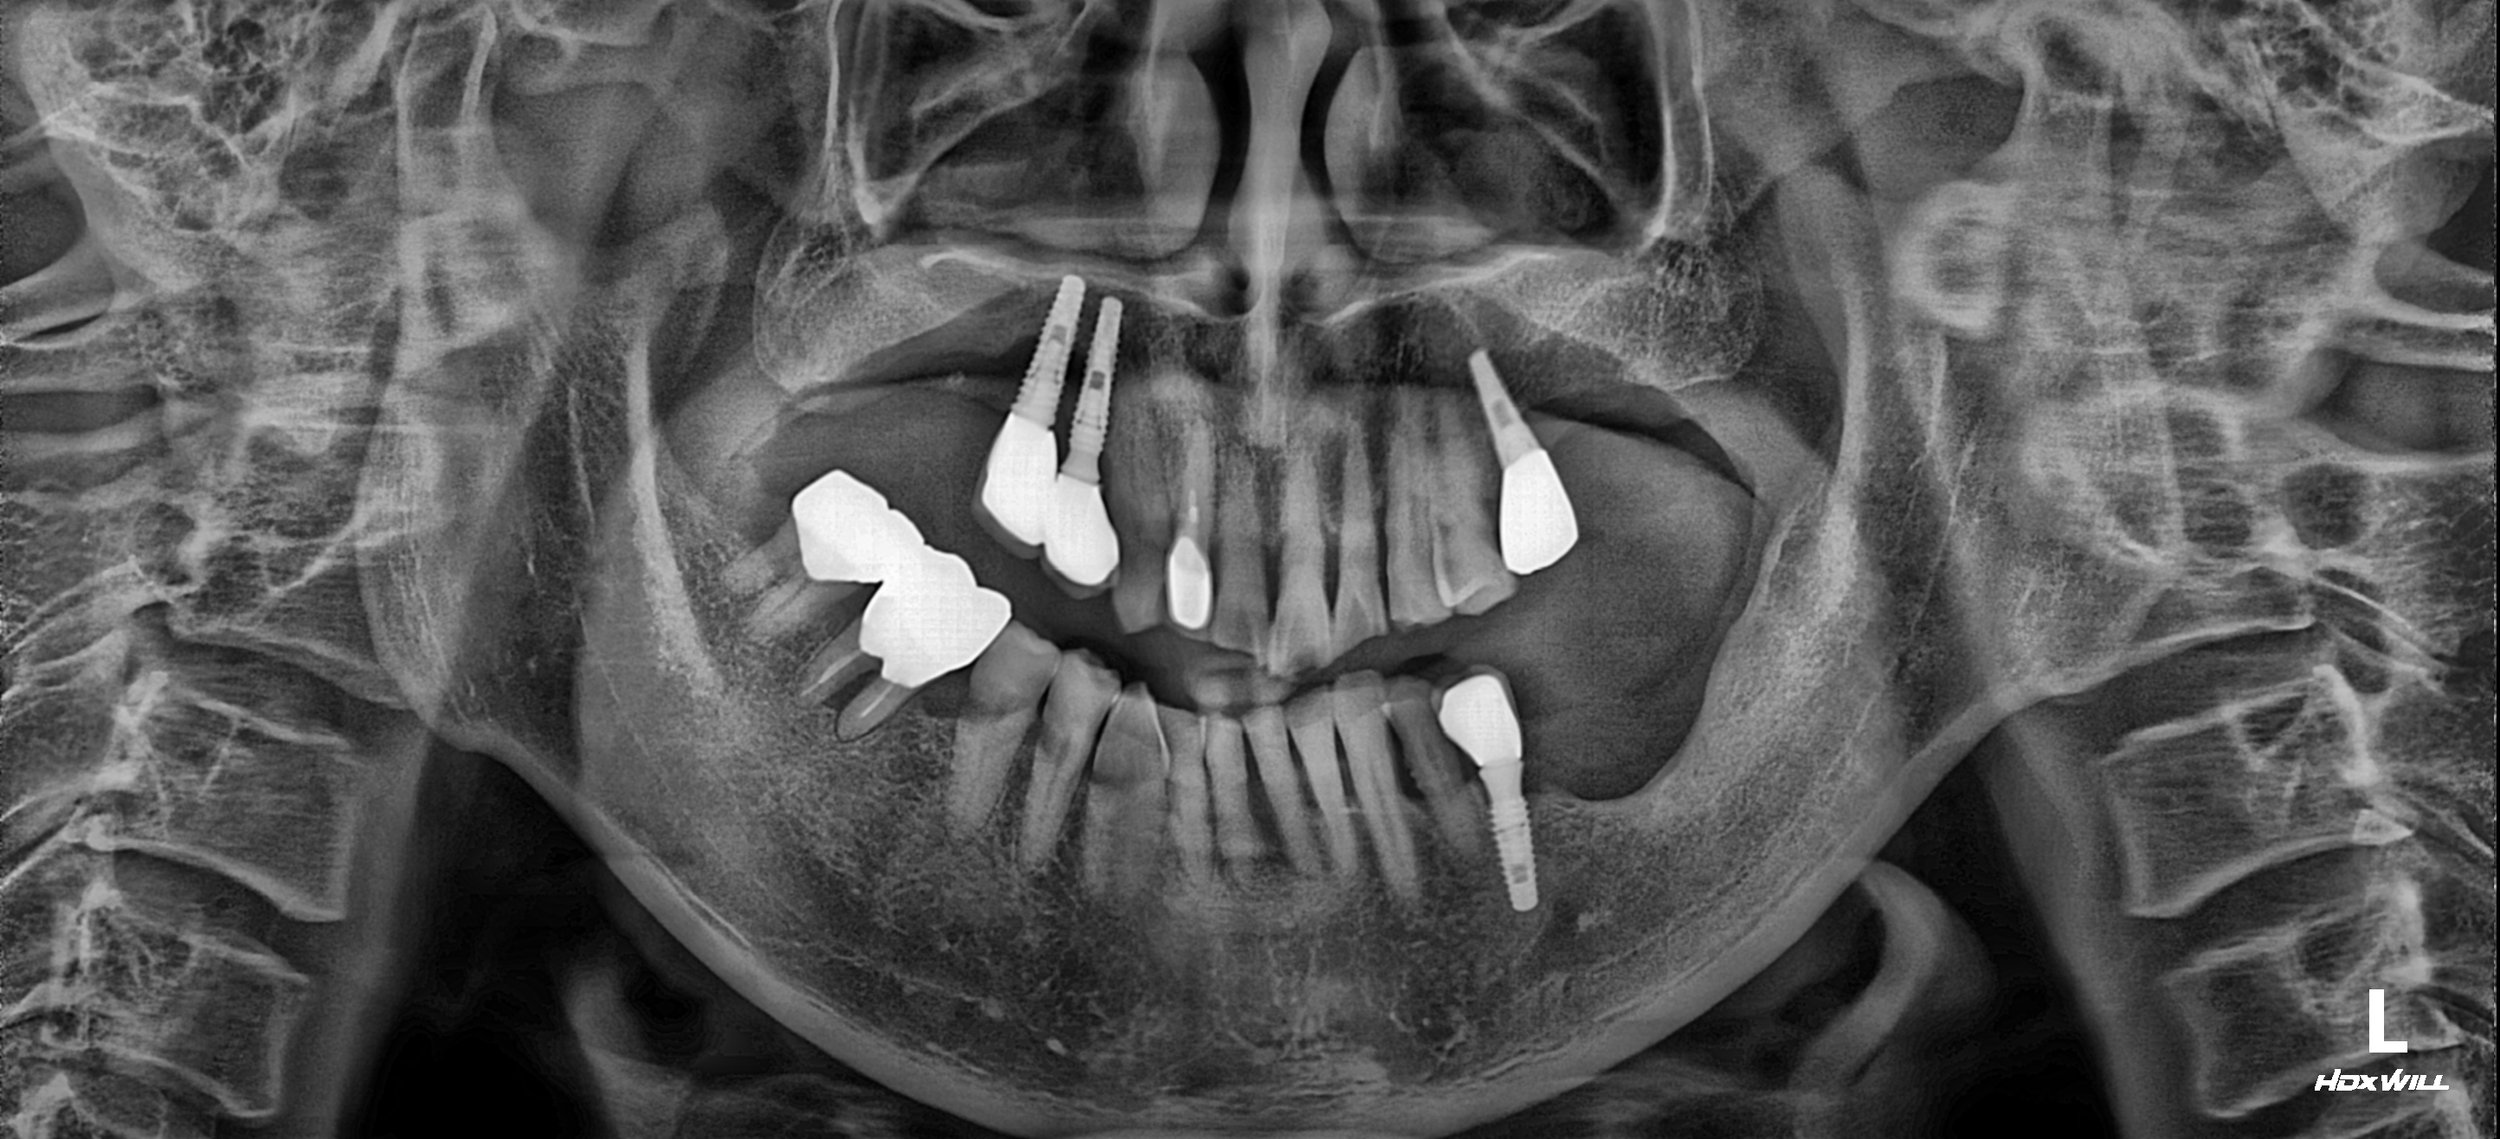

A male patient in his 50s presented with a severely compromised dentition characterized by a complex skeletal Class III tendency and pronounced facial asymmetry. The clinical situation was significantly complicated by a previous implant intervention where implants were placed without addressing the underlying occlusal disharmony. These poorly positioned, "useless" implants had not only failed to function but had actively exacerbated the patient's severe malocclusion.

• Iatrogenic Implant Failure: Existing implants located in positions that made functional restoration impossible, acting as destructive occlusal interferences.

OPG - BEFORE